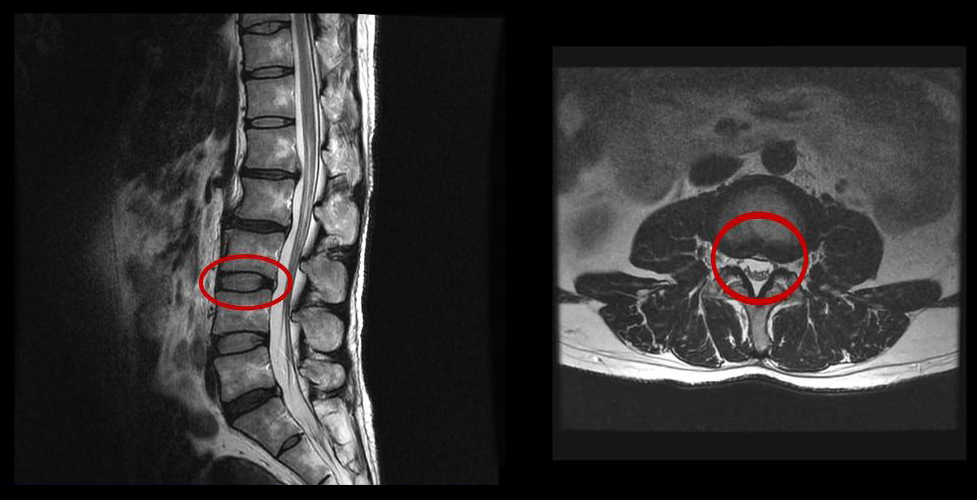

그런데 이 환자분의 MRI를 보면 여러 마디에 퇴행성디스크가 있습니다.

이 환자분은 MRI상으로 거의 대부분 마디의 디스크가 퇴행되고 수핵이 밀려나와 있으며, 정상적인 허리 마디는 4-5번 하나 정도입니다. 그렇기 때문에 MRI만 보면 아마 대부분의 병원에서 허리디스크탈출 또는 퇴행성디스크로 인한 허리통증 및 다리통증으로 진단하고 치료할 것입니다. 이분도 그래서 20년간 그런 치료를 무수히 많이 받았으나 그 어떤 치료도 별 도움이 되지 않았습니다.

이 환자분처럼 오랜 기간 만성적인 허리통증이 있고, 엉덩이가 저리면서 심지어는 양쪽 다리저림까지 있는 환자분들이 많습니다. 그런데 이 환자분의 MRI를 보면 여러 마디의 퇴행성디스크, 디스크탈출, 황색인대의 두꺼워짐, 후관절의 퇴행 등 다양한 병변들을 가지고 있는 걸 볼 수 있는데요. 그렇기 때문에 많은 병원에서 이분을 디스크로 진단하고 거기에 따른 치료가 이루어졌습니다. 그러나 저희가 보기에는 이분의 MRI상으로 보이는 여러 마디의 디스크 문제가 이 환자분이 갖고 있는 증상을 설명할 수 없었습니다.

만성적인 허리통증은 그 원인을 찾기가 매우 힘듭니다. 왜냐하면 만성 허리통증의 대부분은 근육의 기능 문제가 원인인데, 근육의 기능 문제는 MRI상으로는 보이지 않기 때문입니다. 또 양쪽 다리가 저린 이유도 MRI만으로는 알 수 없습니다.